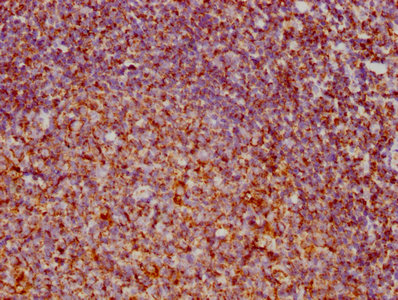

圖片:

應(yīng)用范圍:ELISA, IHC

Application Recommended Dilution IHC 1:20-1:200 -